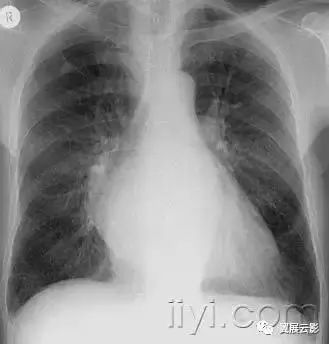

平片和CT:肺实变表现为肺实质密度的均匀一致性增高,导致肺血管和气道壁边缘不清。有时可见含气支气管征。只有在极少数的情况下,肺实变的密度变化有助于鉴别诊断,例如脂性肺炎是密度减低,胺碘酮中毒时密度增高。

图示为多灶性的肺实变。